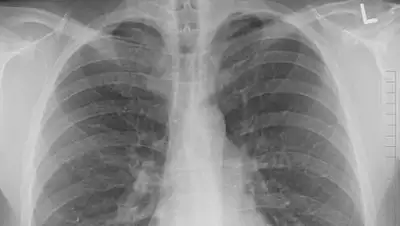

По сравнению с прошлым годом сейчас меньше людей болеют пневмонией и ОРВИ.

Благодаря проведению ранней вакцинации, всеобщему масочному режиму и мерам по дистанцированию, текущей осенью заболеваемость населения пневмонией и ОРВИ имеет устойчивую динамику к снижению, - сообщается на официальном сайте премьер-министра РК.

Например, только за октябрь, по сравнению с сентябрем, число заболевших пневмонией уменьшилось на 26% с 24,8 тыс. до 18,3 тыс., а острой респираторной вирусной инфекцией — на 7,6% с 286,8 тыс. до 265,3 тыс. человек.

По сравнению с прошлым годом, заболеваемость ОРВИ снизилось в 1,7 раза — с 441,2 тыс. в октябре 2019 г. до 265,3 тыс. в октябре.